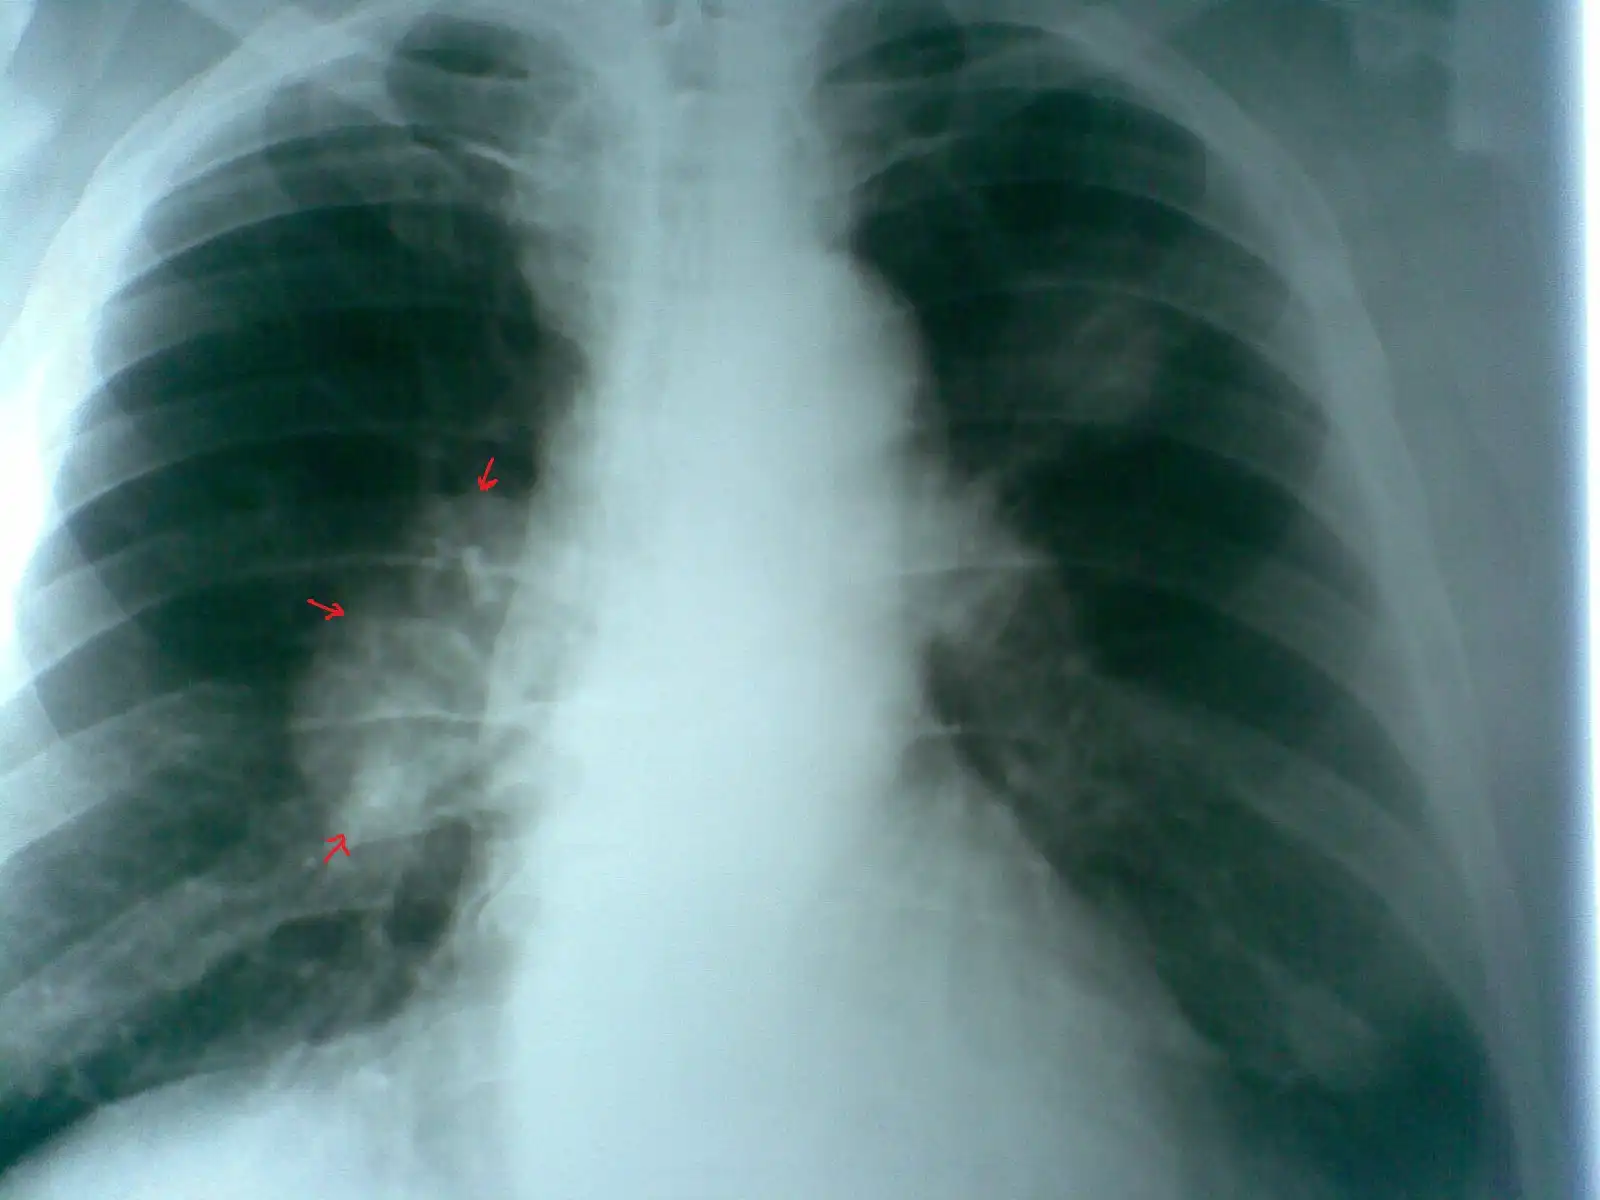

Пациент № 1: